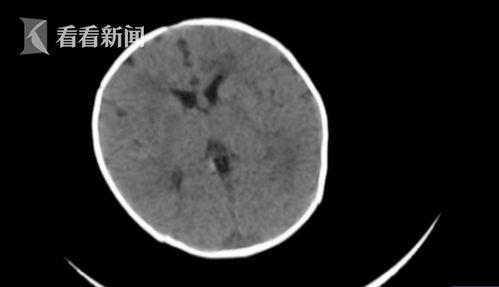

视频中,医生详细介绍了脑出血的症状和治疗方法。据医生介绍,脑出血是指脑内血管破裂,血液流入脑组织或脑室,导致脑组织受损。脑出血的症状包括剧烈头痛、恶心呕吐、意识障碍、肢体瘫痪等。如果不及时治疗,患者可能会出现生命危险。